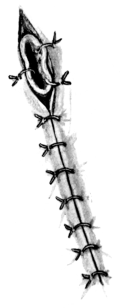

| 266. | Laryngotomy Canula fitted with Inner Tube | 513 |

| 269. | Tubes for Tracheotomy | 527 |